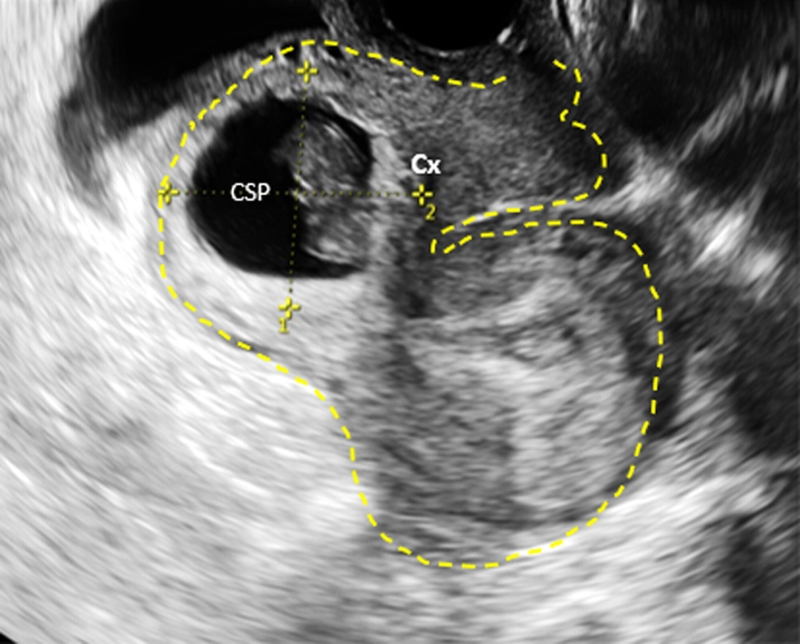

Trước đây, việc thai bám ở sẹo mổ lấy thai là một hiện tượng hiếm, tuy nhiên với sự gia tăng việc thực hiện mổ lấy thai, số trường hợp thai bám vào vết mổ cũng đang tăng lên. Sự áp dụng rộng rãi siêu âm ngã âm đạo để đánh giá thai kỳ sớm đóng góp vào việc chẩn đoán sớm và giảm rủi ro khi điều trị.

Triệu chứng sớm của bệnh lý này đôi khi giống như thai kỳ bình thường, với trễ kinh và có thể đi kèm với đau bụng và huyết âm đạo không bình thường. Để chẩn đoán, việc kiểm tra bằng siêu âm là quan trọng. Trong trường hợp xuất huyết vào ổ bụng ở giai đoạn muộn, có thể xuất hiện các triệu chứng nặng nề như da xanh, niêm nhạt, mạch nhanh, huyết áp tụt, suy nhược.

Khi thai phát triển, việc túi thai kết nối với vết sẹo tử cung trở nên không ổn định do áp lực ngày càng tăng. Điều này tăng nguy cơ vỡ tử cung. Đối với phụ nữ có lịch sử sinh mổ, quan trọng để đến kiểm tra sớm khi mang thai lại, nhằm xác định vị trí chính xác của thai. Phát hiện kịp thời thai bám ở sẹo mổ lấy thai giúp duy trì khả năng sinh sản.